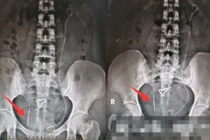

Đi khám tại Bệnh viện Đại học Y Hà Nội, các bác sĩ phát hiện một ổ áp xe vùng hố chậu phải. Đáng chú ý, một đầu tăm nằm trong thành bụng, một đầu nằm trong ruột non. Bằng các phương tiện siêu âm và chụp cắt lớp, các bác sĩ nhận định chiếc tăm đã xuyên qua thành ruột non, một đầu găm vào thành bụng và một đầu vẫn nằm trong lòng ruột; đặc biệt đầu ngoài chiếc tăm gây viêm ở thành bụng tạo thành ổ áp xe.